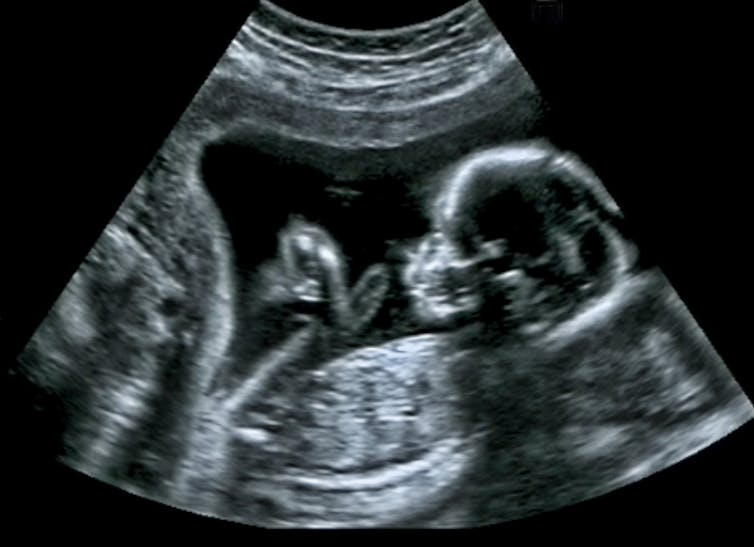

Ultrasound

Ultrasound uses sound waves to generate a medical image of human anatomy, and has no known detrimental effects. The frequency of ultrasound is higher than the sound wave frequencies that can be detected by human hearing. Sound waves can only travel through a medium, so a water-based gel needs to be applied to the skin, which allows the ultrasound to be transmitted from the transducer (or probe - the thing that’s moved over the area being scanned) into the body.

Ultrasound reflects sound waves differently from all the different tissues within the body, the more dense a tissue is, the more sound waves are reflected and returned to the transducer. Where tissue is less dense, part of the sound waves will be returned to the transducer and part of the ultrasound will be transmitted through this tissue until it reaches a different type of tissue and the process continues (partly reflected and partly transmitted).

When ultrasound waves return to the transducer, the sound waves are converted into an electrical signal, which is then digitised and reconstructed as an image. The image is formed by calculating the distance from where the reflected sound waves interacted with tissue and the transducer, and is calculated by knowing that in human tissue, ultrasound travels at approximately 1,540 metres per second.

For many ultrasound imaging examinations, patients are asked to hold their breath so internal organs remain still while imaging is taking place. They may also be asked to move into certain positions.

In addition to providing structural information on how anatomy is arranged, ultrasound has the added benefit of providing biomechanical and functional information, as it can also image in real time and observe muscles and tendons moving.

Ultrasound imaging has two important applications. The first is in pregnancy and the second is to see if muscles and tendons are in some way damaged.